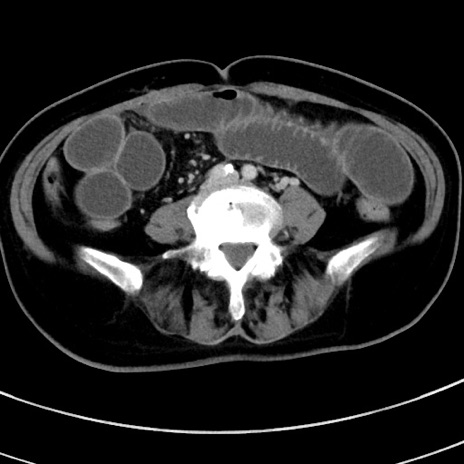

冠状断像